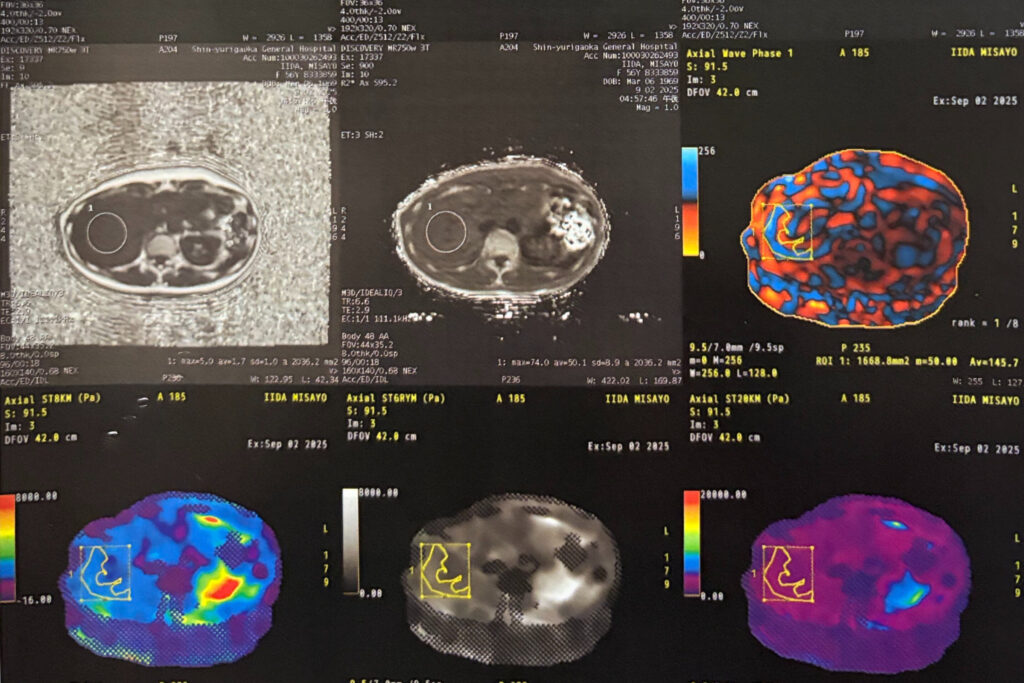

詳細な結果は3週間から1カ月後に自宅に郵送されますが、検査後すぐに、消化器内科部長の今城健人先生が画面を見ながら、結果を解説してくれました。

モニター画面に、まずは私の内臓の断面図が映し出されました。

続いて、私の肝臓の画像が2つ並んでいます。左は波画像で、しっかり波が肝臓に入っていっていることを確認する画像、右は肝臓の硬さを確認する画像です。

「飯田さんの肝臓は真っ青で、脂肪は全くありませんね」。

今城先生が、硬さを確認する画像を見ながら明るいトーンで話します。

「問題なし」の結果にひゃー、良かった! 安どのため息。数値で示されてもイメージが湧きづらいのですが、色付きの画像で見ると、一目瞭然、納得感が違います。ひとまず、ホッとしました。

「肝臓が硬いと、肝硬変や肝がんに進むリスクがあります。硬さは色で表示され、青・緑は柔らかく、黄・赤になるほど危険です」(今城先生)。

私の数値は、2.43kPa(正常~軽度、A判定)。数字よりも画像を見ると、直観で分かります。

上の画像の左下でもわかるように、私の肝臓は真っ青で、肝臓が柔らかい状態です(その画像の赤い部分は胃やその他の臓器の硬い部分)が、「線維化が進行してくると、緑→黄→赤と色が変わってきます」(今城先生)。